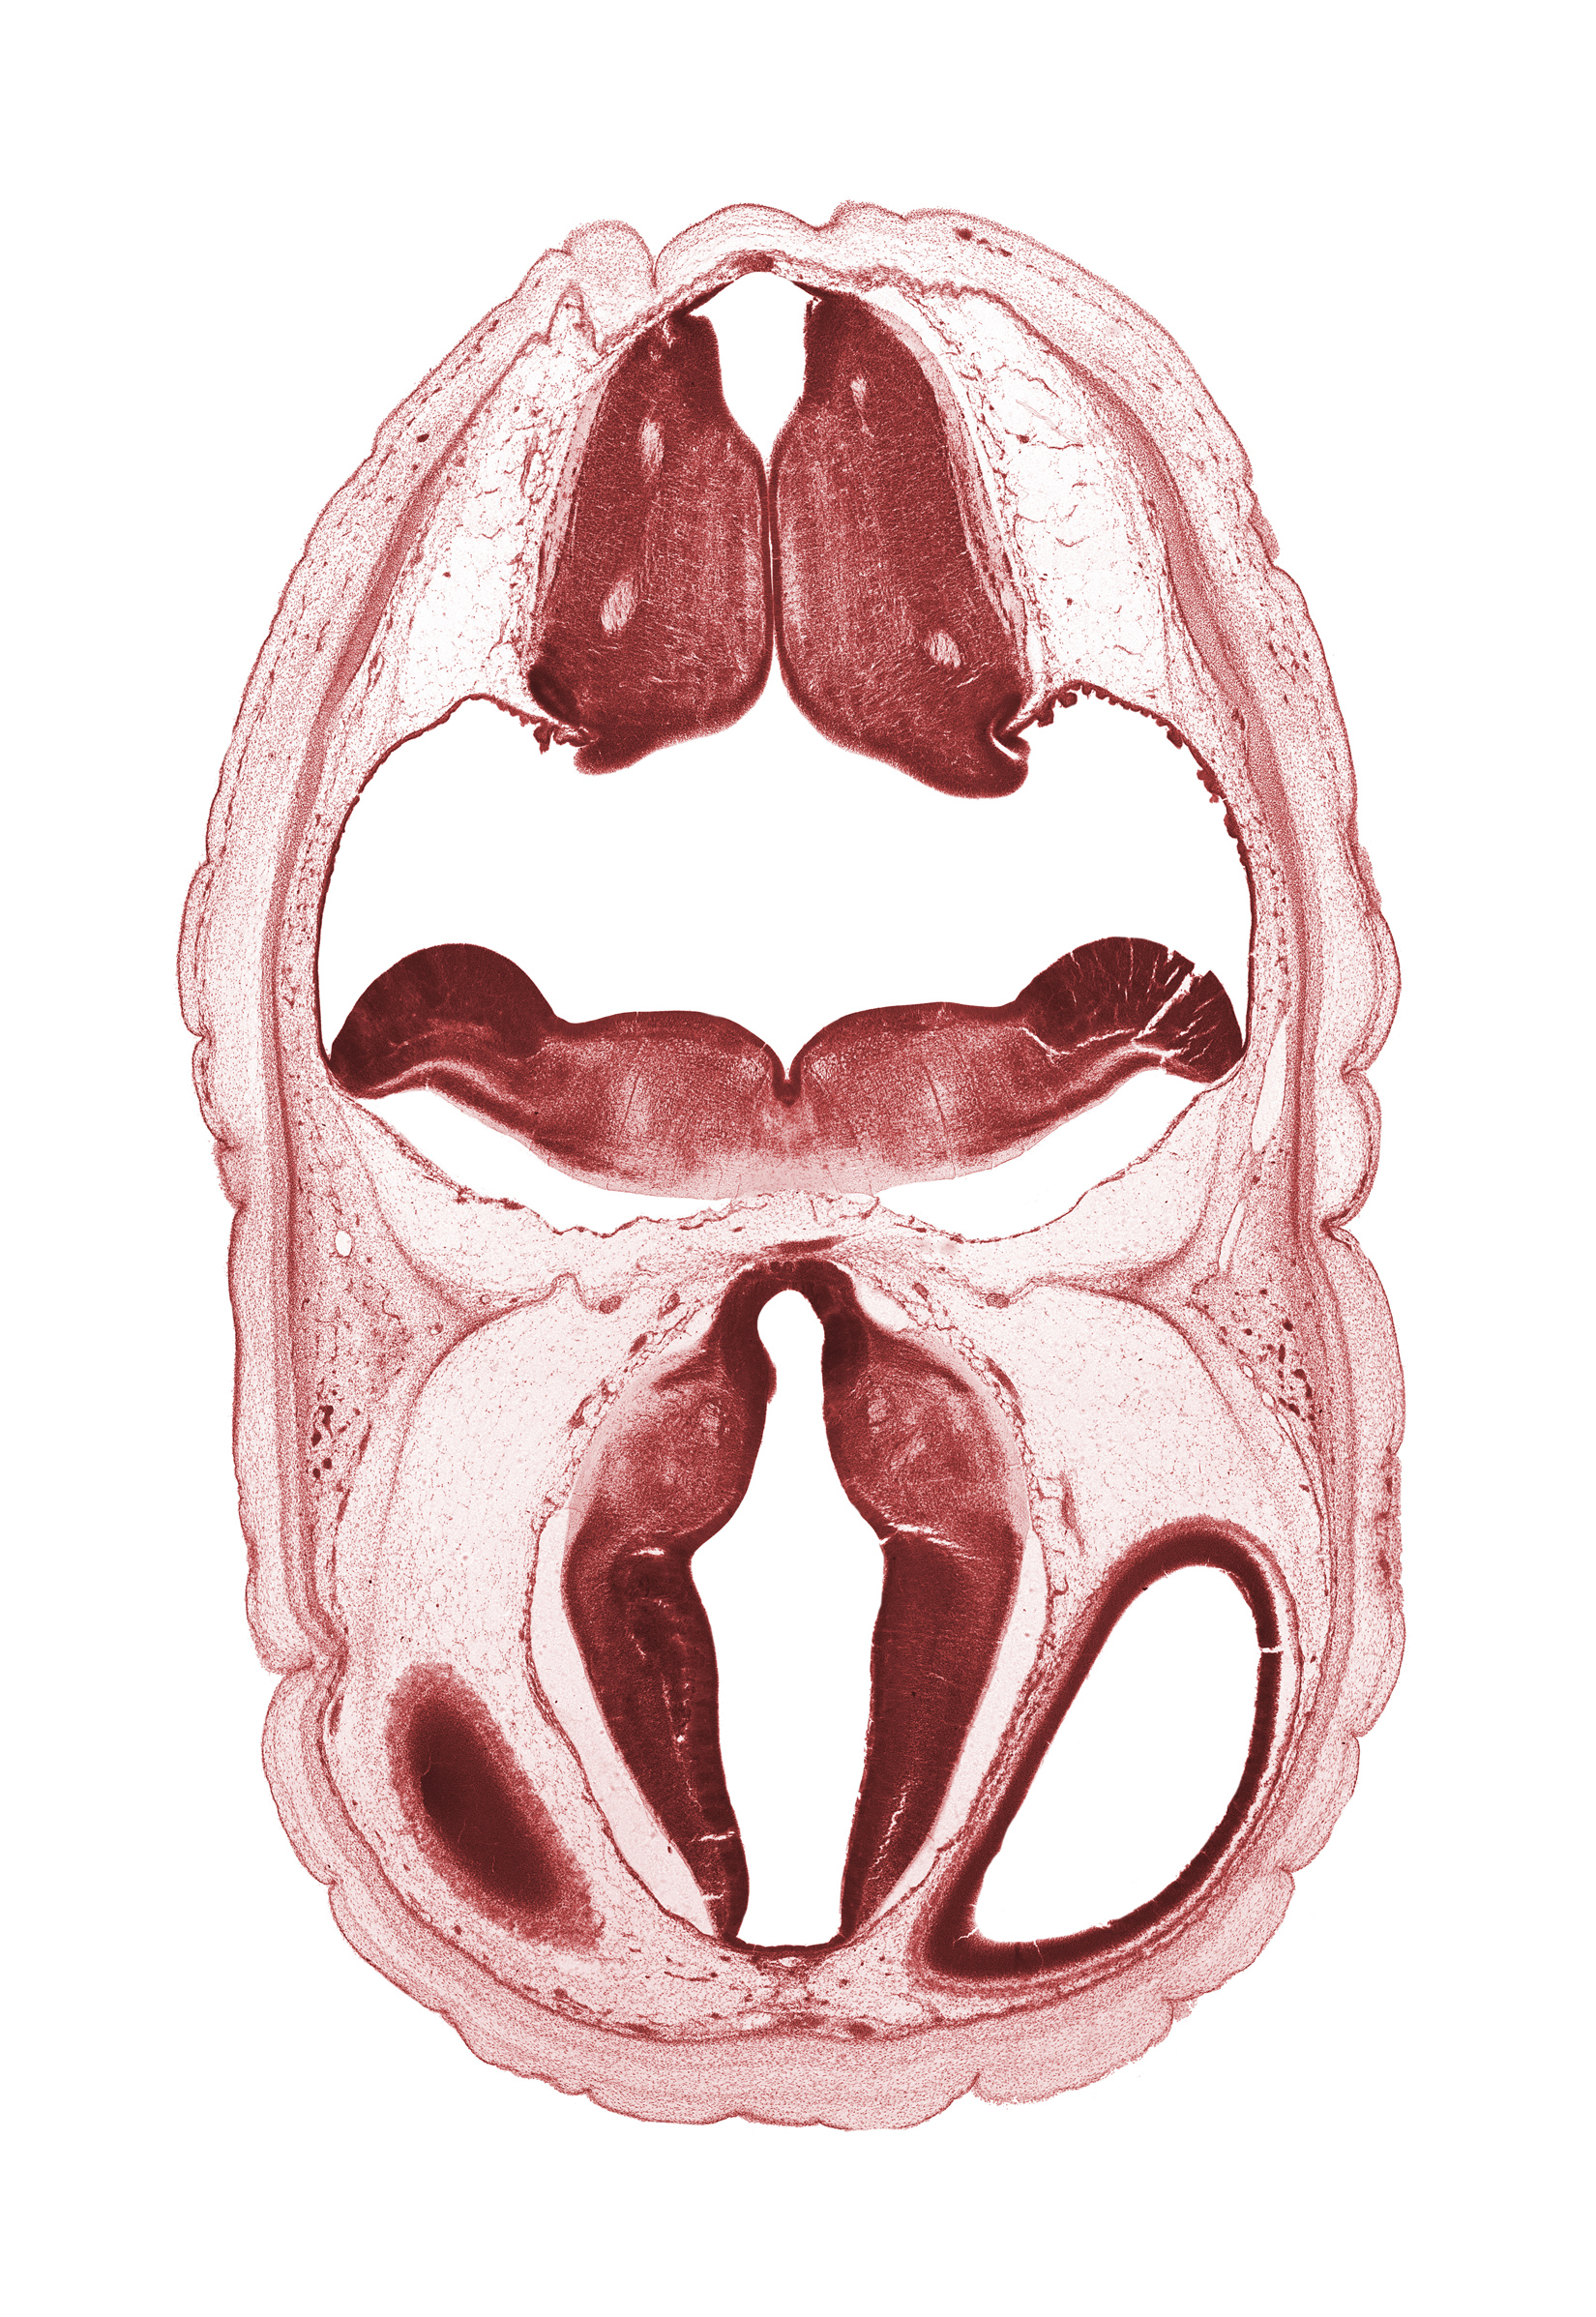

Carnegie Embryo #4090   |   Location: 5-7

Keywords: artifact space(s), diencephalon, dorsal thalamus, dural band for tentorium cerebelli, fiber tract, hypothalamus, metencephalon, myelencephalon, obex, oculomotor nerve (CN III), osteogenic layer, roof plate, roof plate of diencephalon, subarachnoid space, ventral thalamus, wall of cerebral vesicle (hemisphere)

Source: The Virtual Human Embryo.